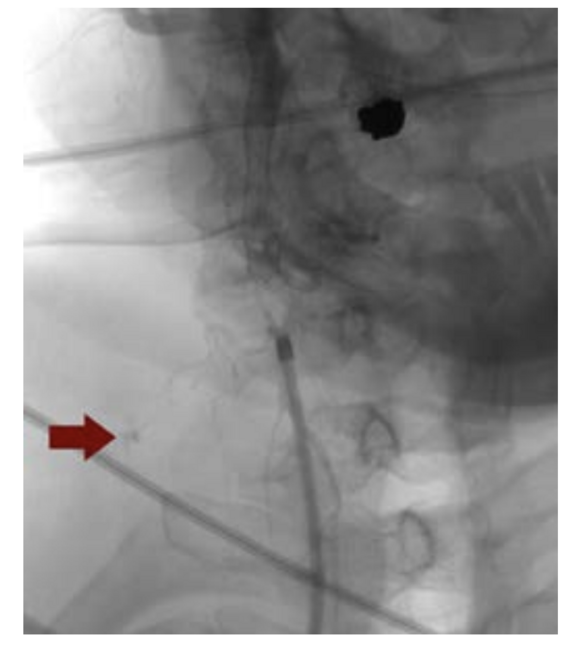

A Runthrough extra floppy wire was advanced to the distal internal carotid artery, and the spider FX filter wire was secured 3 centimeters distal to the ICA lesion. A Protege Rx carotid stent was then deployed followed by post dilation with a 5.0 x 20 mm balloon (Figure 1). The intraoperative course was smooth and then the patient was transferred to the ICU.